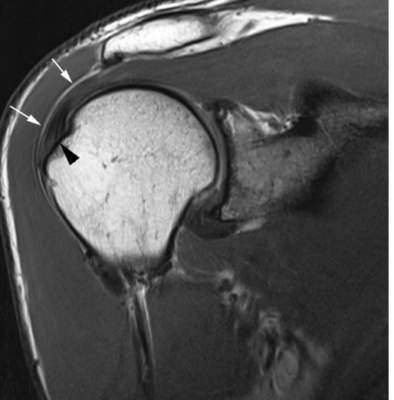

Chụp cộng hưởng từ (MRI):

Dành cho nghi ngờ rách CCX và không cải thiện triệu chứng dù điều trị đầy đủ 3-6 tuần. MRI có thể phát hiện nhiều tổn thương CCX từ thoái hoá đến rách hoàn toàn. MRI là phương pháp chẩn đoán hình ảnh tốt hơn nhiều phương pháp khác, đặc biệt là rách một phần. Nó có thể phát hiện rách trong gân hoặc rách gân mặt bao hoạt dịch, mà những phương pháp khác khó phát hiện. MRI cũng có thể ghi nhận những tổn thương mô mềm khác như cơ, dây chằng, bao khớp, sụn khớp, tuỷ xương.